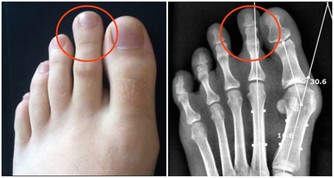

徵兆四:胃部脹痛

有些人由於患過胃病,所以很容易把胃病與心臟病引起的胃部不適混為一談,

心臟病引起的胃痛很少會出現絞痛和劇痛,壓痛也不常有,只是有一種憋悶、脹滿的感覺!